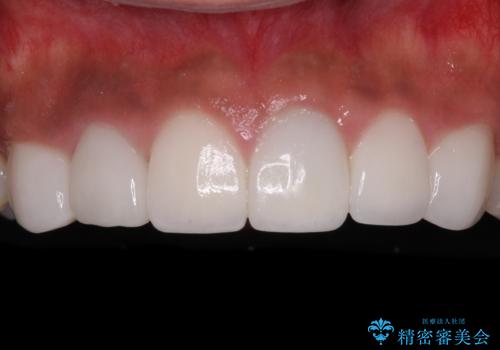

[前歯 セラミック治療] すぐに前歯が取れる きちんと治療して欲しい

![[前歯 セラミック治療] すぐに前歯が取れる きちんと治療して欲しいの症例 治療後](https://seimitsushinbi.jp/wp/wp-content/uploads/2021/01/1c3b62c3a0de497eade34ec62d821d52-500x350.jpg?v=1609914963)